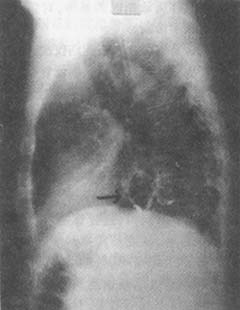

X线检查:内腔镜检查为诊断食管裂孔疝的主要方法。钡餐检查最为常用,但需用手法帮助才能显示出疝。令患者左侧卧位,头低,当胃内充满钡剂后,以手压迫腹部,令患者用力摒气,此时可出现裂孔疝指征:膈下食管段(腹段)变短增宽或消失,贲门部呈现幕状向上牵引,膈上可见胃囊(图1、2),膈上出现食管胃狭窄环(Schatzki环形狭窄),此环相当于鳞状上皮和柱状上皮交界处(图3)。有食管狭窄时,粘膜变形,管腔缩窄。短食管时则膈上有粗大的胃粘膜,食管胃交界点因瘢痕收缩可上升至第9胸椎水平。作钡餐检查时,用以刺激返流的手法中,以Muller手法比较有效(呼气后关闭声门,再用力吸气以增加胸内负压,促使胃内钡剂反入食管);有人用“饮水”方法;让病人喝水入胃,与钡剂相混合,然后挤压腹部。在有条件的医院,应将上胃造影做成录像带,以便反复检查。多数人认为有裂孔疝时不一定有X线上的返流征象;而有返流征象时不一定有裂孔疝。有幕状牵引者是否诊断为裂孔疝,意见尚不一致。正常食管壶腹不应误认为裂孔疝,弥漫性食管痉挛可以发生裂孔疝和胃液返流征象。硬皮病和贲门失弛缓症时食管缺乏蠕动功能,也要和裂孔疝相区别。如发现食管有机械性缩窄,应作多方面观察。以区别新生物、溃疡性良性缩窄或食管动力性疾病,一般认为,放射科医生关于缩窄原因的报告只能作为诊断时的参考,对每位病人必须有组织学诊断。

图1 食管裂孔疝X线

钡剂造影:胃粘膜呈幕状牵引

图2 食管裂孔疝X线

钡剂造影:膈上见胃囊